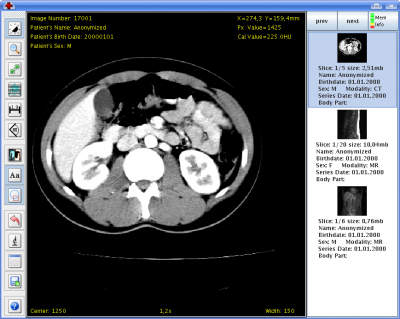

Visionneuse DICOM Fig. 2: Visionneuse DICOM

La visionneuse intégrée fournit des fonctions pour faire des zooms de l'image en utilisant la molette de la souris et pour facilement naviguer à travers les différentes images d'une série. Elle fournit également des outils pour mesurer des tailles et des angles ainsi que pour inverser l'image disponible. Une aide intégrée explique comment utiliser les touches de fonction de la souris pour exécuter des fonctions les plus importantes.